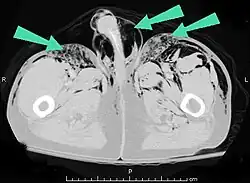

Sinais e sintomas de enfisemas subcutâneos espontâneos variam de acordo com a causa, mas geralmente está associado a inchaço do pescoço e dor torácica, podendo também envolver dor de garganta, dor no pescoço, dificuldade para engolir, chiado no peito e dificuldade para respirar.[3] Um Raio-X pode mostrar ar no mediastino, no meio da cavidade torácica.[3] Um caso significativo de enfisema subcutâneo é fácil de detectar ao palpar a pele sobrejacente. A textura vai parecer de papel de seda.[4] Tocar nas bolhas faz com que elas se movam e, às vezes, produzam um ruído crepitante.[5] As bolhas de ar, que são indolores e parecem pequenos nódulos ao toque, podem estourar quando a pele acima delas é palpada.[5] Os tecidos que circundam o enfisema estão geralmente inchados . Quando grandes quantidades de ar vazam para os tecidos, o rosto pode inchar consideravelmente.[4] Em casos de enfisema subcutâneo ao redor do pescoço, pode haver uma sensação de inchaço no pescoço, e o som da voz pode mudar.[6] Se o enfisema for particularmente grande ao redor do pescoço e do tórax, o inchaço pode interferir na respiração. O ar pode viajar para muitas partes do corpo, incluindo o abdômen e membros, porque não há separações no tecido adiposo da pele para evitar que o ar se mova.[7]

O enfisema pode produzir protuberâncias, como nódulos móveis com ruídos crepitantes a palpação. Em uma radiografia de tórax, o enfisema subcutâneo pode ser visto como estriações radioluzentes (escuras) nas áreas com músculos. O ar nos tecidos subcutâneos pode interferir na radiografia do tórax, potencialmente obscurecendo condições graves, como o pneumotórax. Também pode reduzir a eficácia do ultrassom.[8] Também é visível na tomografia e na ressonância magnética como bolhas escuras.

O enfisema subcutâneo é geralmente benigno.[1] Na maioria das vezes, o próprio enfisema não precisa de tratamento (embora as condições a partir das quais ele resulta precisem); no entanto, se a quantidade de ar for grande, isso pode interferir na respiração e ser desconfortável.[9] Quando a quantidade de ar expelida das vias aéreas ou do pulmão se torna enorme, geralmente devido à ventilação com pressão positiva , as pálpebras incham tanto que o paciente não consegue enxergar. Além disso, a pressão do ar pode impedir o fluxo sanguíneo para a aréola da mama e pele do escroto ou dos lábios. Isso pode levar à necrose da pele nessas áreas. Estas são situações urgentes que requerem descompressão rápida e adequada.[10][11][12] Casos graves podem comprimir a traquéia e requerem tratamento.[13]